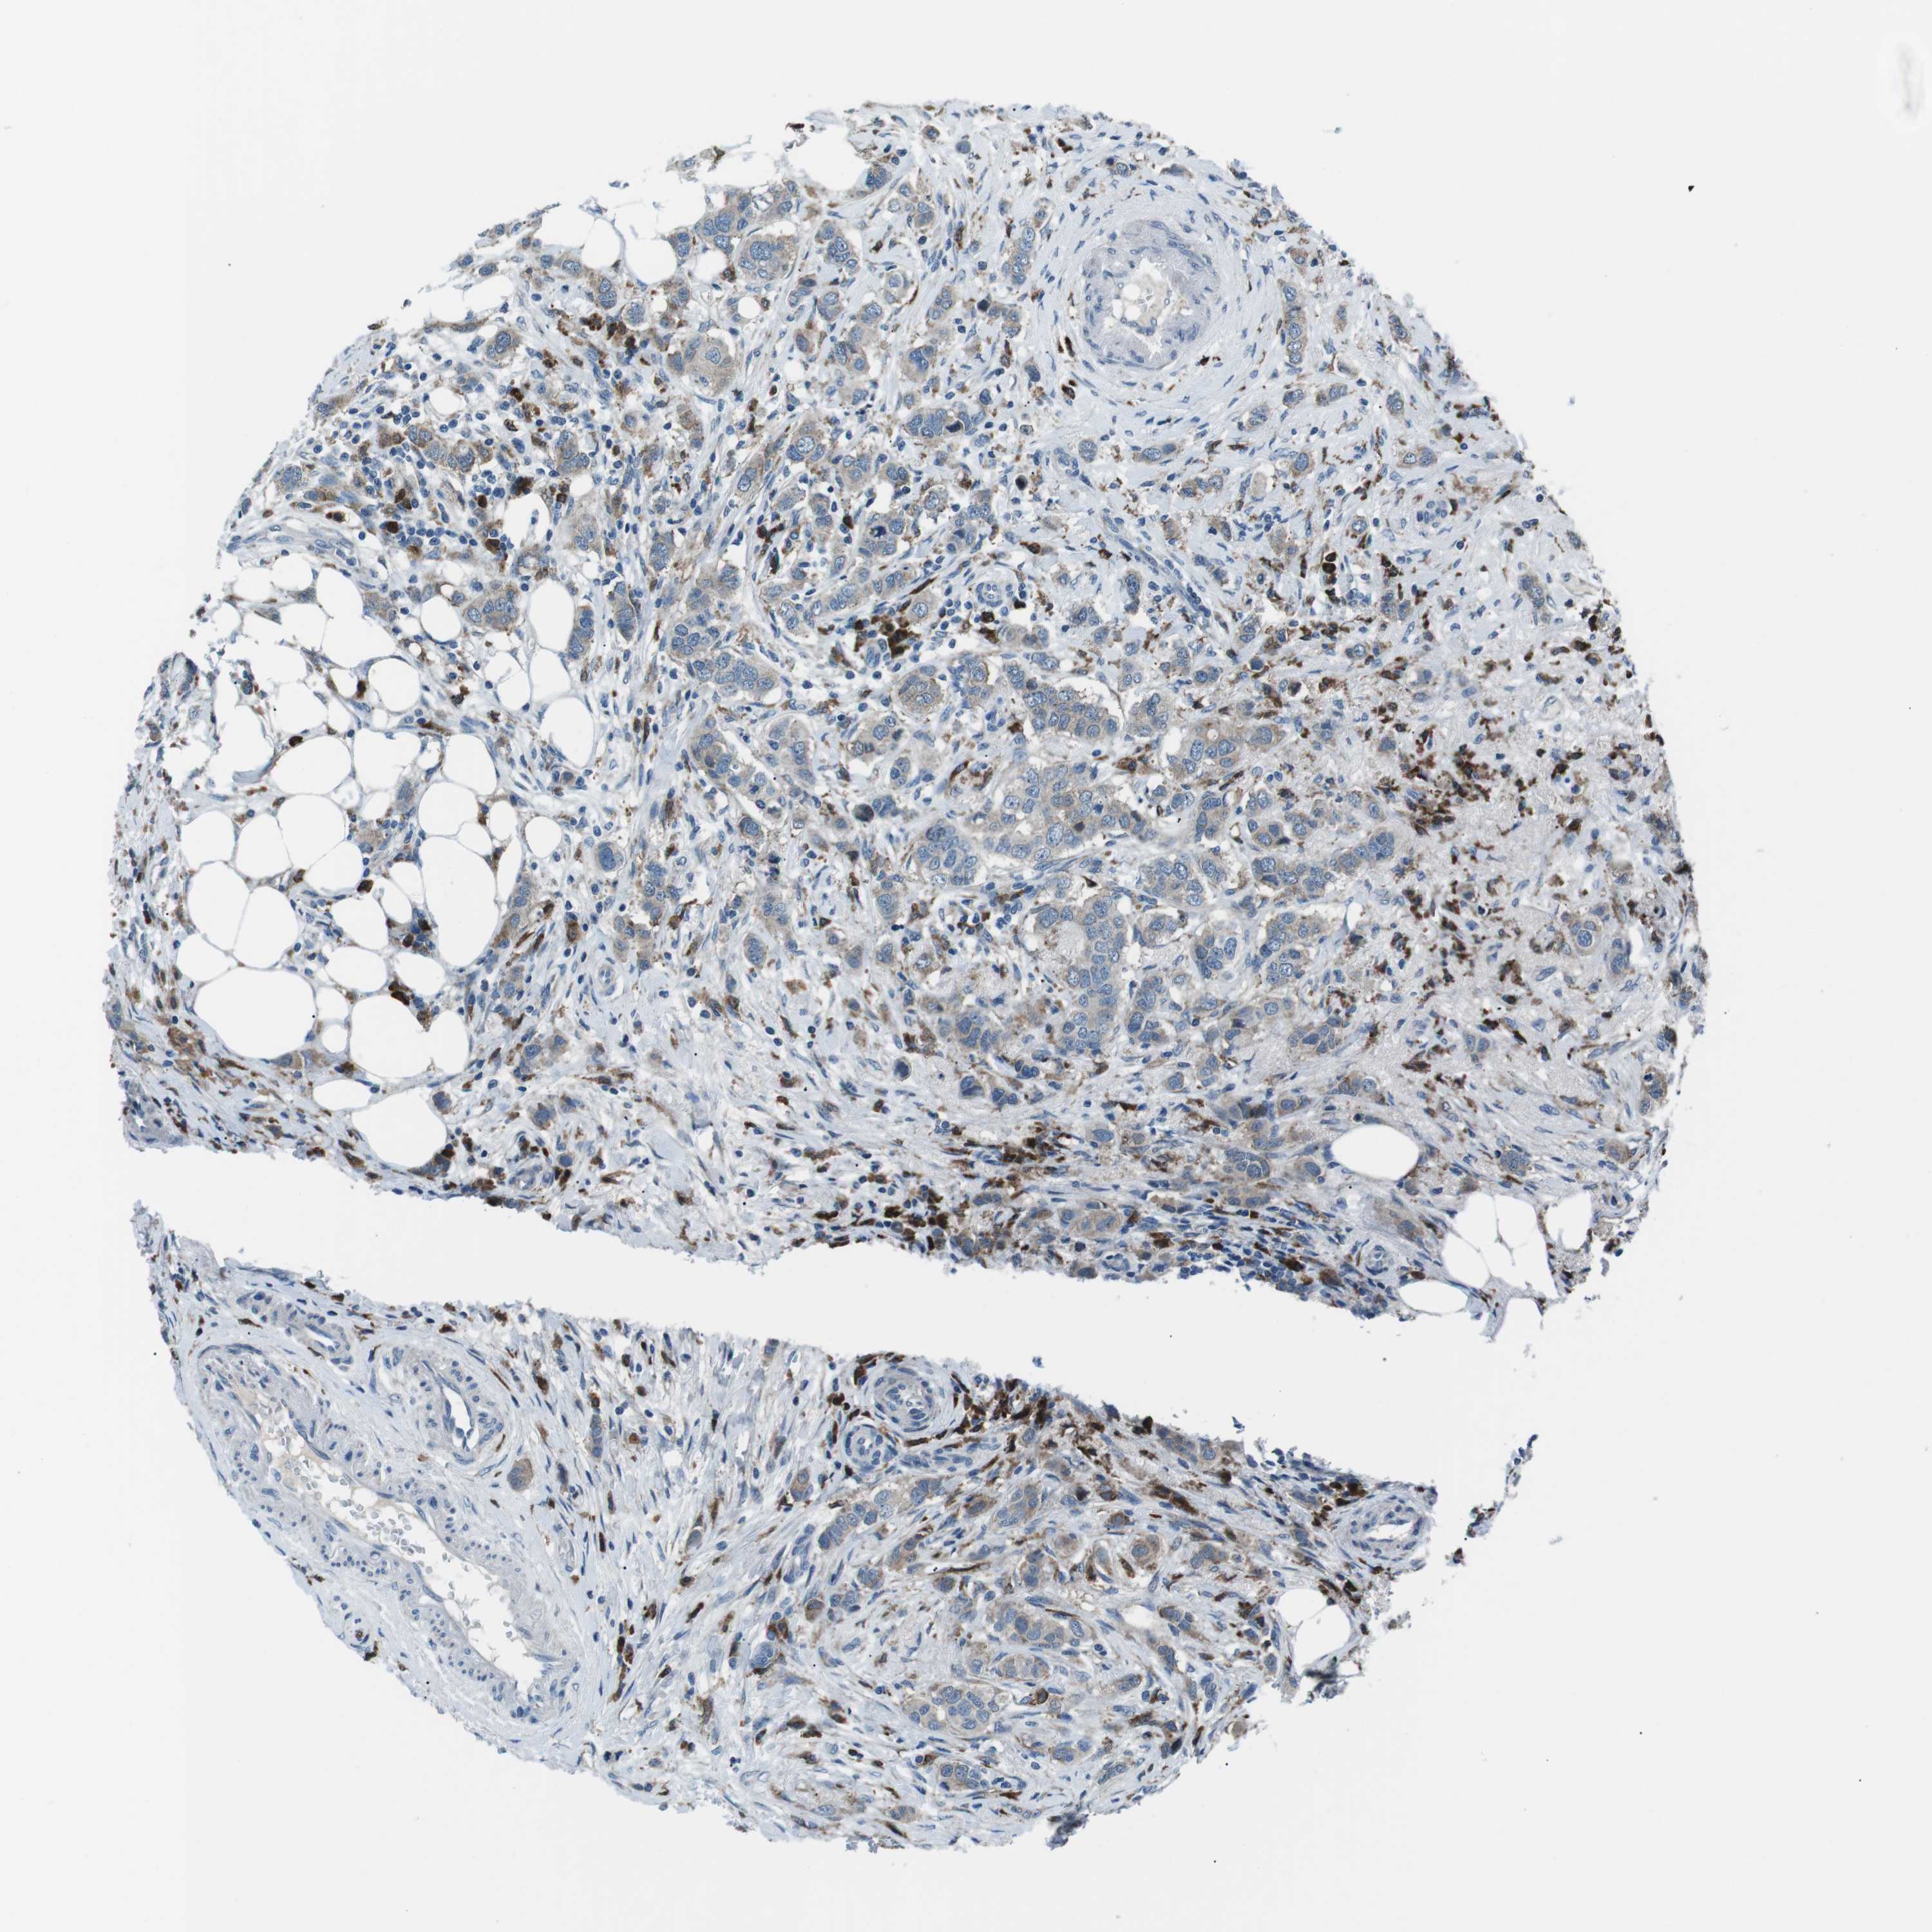

CANCER BREAST CANCER Show tissue menu

BRCA TCGA BRCA VALIDATION PROTEIN EXPRESSION